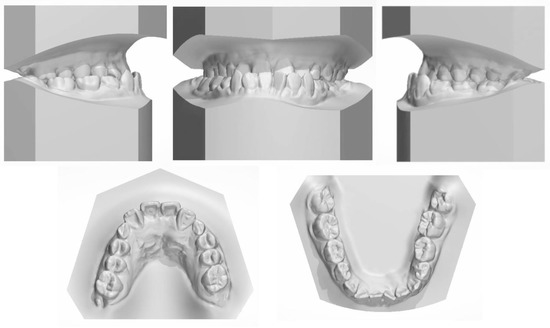

2.5. Treatment Results

All the initial treatment objectives, including occlusion, periodontal health, and facial esthetics, were achieved by a satisfactory multidisciplinary approach, partly due to the cooperation of the patient. The facial photographs showed a pleasant profile and a harmonious smile. The patient was satisfied with the facial improvement, and she became more confident (Figure 7). Posttreatment intraoral photographs and dental casts (Figure 8) showed bilateral Class II molar and Class I canine relationships with an ideal overjet and overbite. The gingiva tissue in the mandibular anterior region was evidently augmented, which indicated lower periodontal risks.

The final panoramic radiograph confirmed parallel roots with no apparent root resorption. Cephalometric analysis (Figure 9 and Table 1) indicated a normal anteroposterior (AP) relationship (ANB, from −4° to 1.3°) and decreased lower third (FMA: from 26.6° to21.5°; Na-Me: from 111.8 mm to 103.7 mm). Furthermore, the distance from the upper and lower lips to the E-line were significantly decreased, which helped improve the soft tissue profile.

The 8-year follow-up photographs showed excellent stability of the occlusion and the profile (Figure 10). The pretreatment, posttreatment, and follow-up cephalometric superimposition revealed a significant improvement and stability in the facial profile and the skeletal and dental relationship. Superimposition of the posttreatment and retention digital dental models indicated generally stable results (Figure 11).

Figure 8. Posttreatment dental casts.